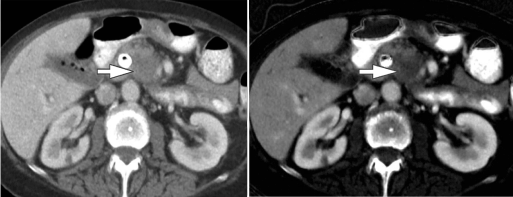

Liver lesion characterization

Evaluation of little liver lesions on typical CT is typically a diagnostic plight. Sub centimeter lesions area unit typically very little to characterize, leading to the necessity of a lot of investigations with tomography or diagnostic test. Cysts are typically differentiated from metastases (small hypodense masses) on iodine pictures in Associate in the extremely DECT scan as a result of a metastasis will uptake iodine whereas a cyst will not (Figure 4) [20].

Figure 4. A 65-year-old man with a history of the malignant neoplastic disease. Contrast-enhanced Porto venous section single energy CT pictures show tow small rounded hypodense lesions in internal organ segments IV (arrow in A) and VII (arrow in B), that are really similar in look. Iodine material decomposition pictures reveal the varied nature of the tow lesions. the phase IV clinical trials lesion demonstrates no uptake of iodine and is so a cyst (arrow in C), whereas the section VII lesion demonstrates iodine uptake (arrow in D) and is so a metastasis.